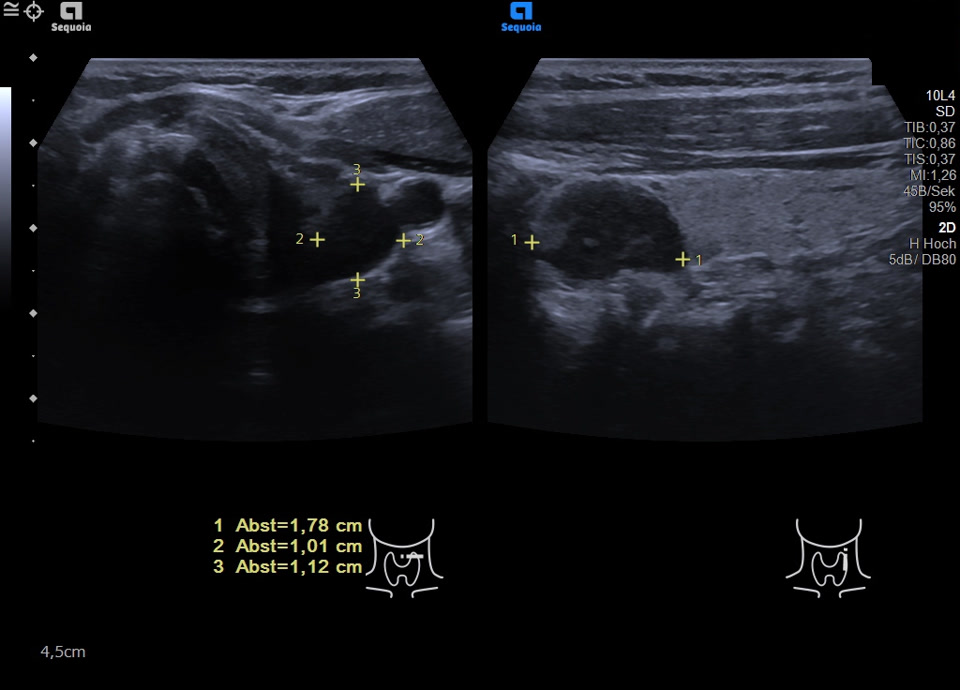

Nebenschilddrüse

• Nebenschilddrüsenadenom

Onkozytäres Nebenschilddrüsenadenom kaudal an die Schilddrüse angrenzend, histologisch gesichert